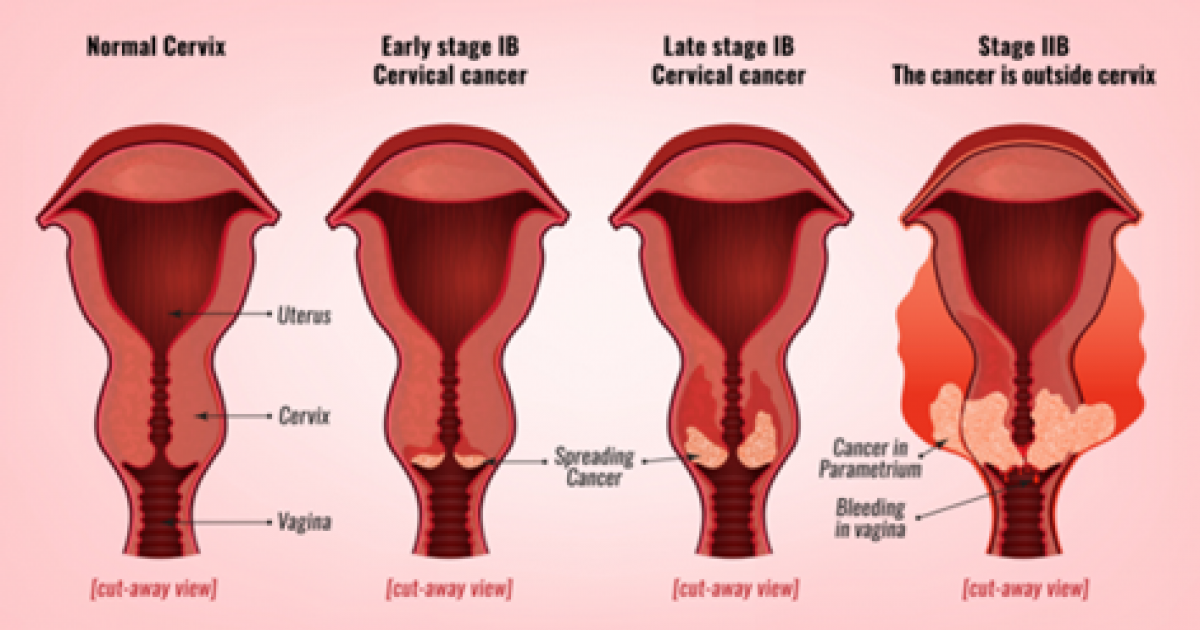

You may strengthen the body's immune system and quite simply create resistance to an hpv infection in basically just a few months, prior to the time that it could originate any important. Ad all cervical cancer treatments are not the same is what you've tried not working? Learn about the stages of cervical cancer and what they mean.